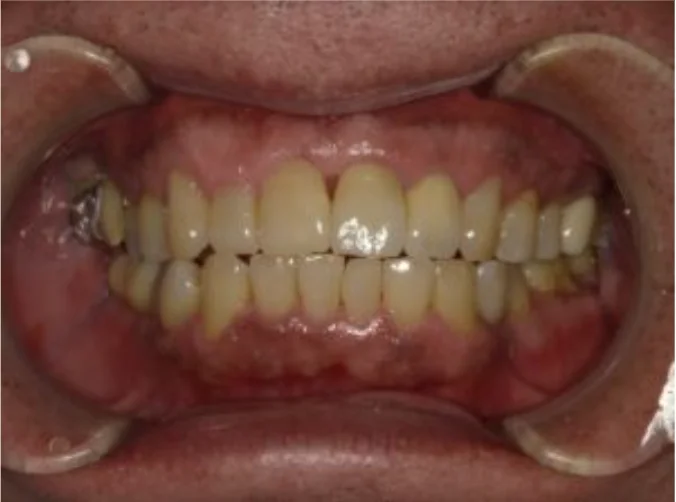

Before

After

ひどい歯周病で治すのが難しい、と言われた歯に歯周組織再生療法を行い改善(70代女性)

約1年 / 総額150,000円リスク・副作用:歯周病は一度改善しても、患者さんの心身の健康状態や歯磨き状況によって再発することがあるため、定期的なメンテナンスで維持できるようにしてくことが大切です。